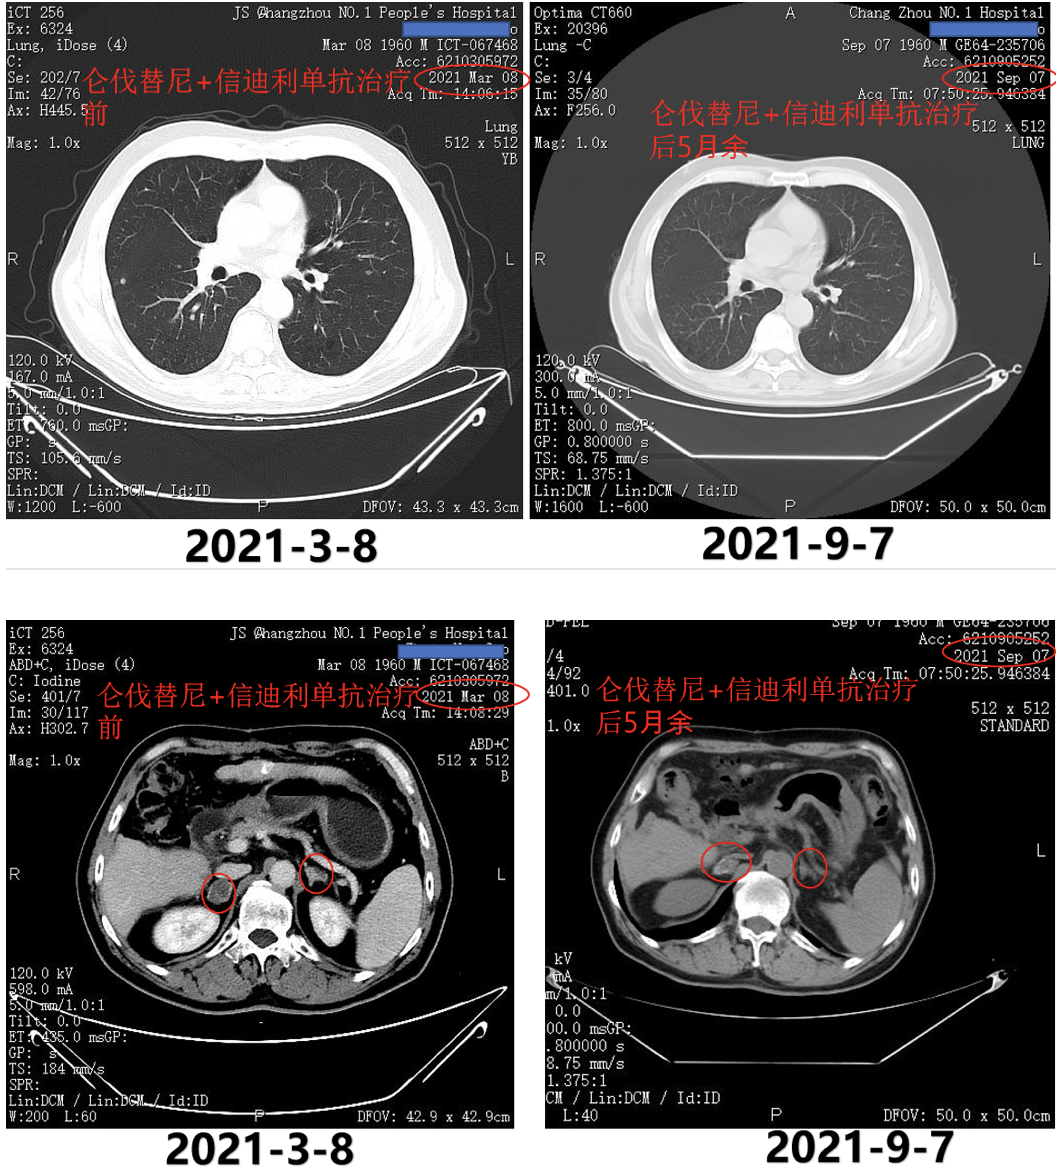

患者全身转移,为Ⅳ期晚期肝癌。2021年3月10日行第3次介入治疗(图6)。2021年3月15日即第3次TACE术后5天AFP为1173ng/ml。

图6.2021年3月10日行第3次介入治疗